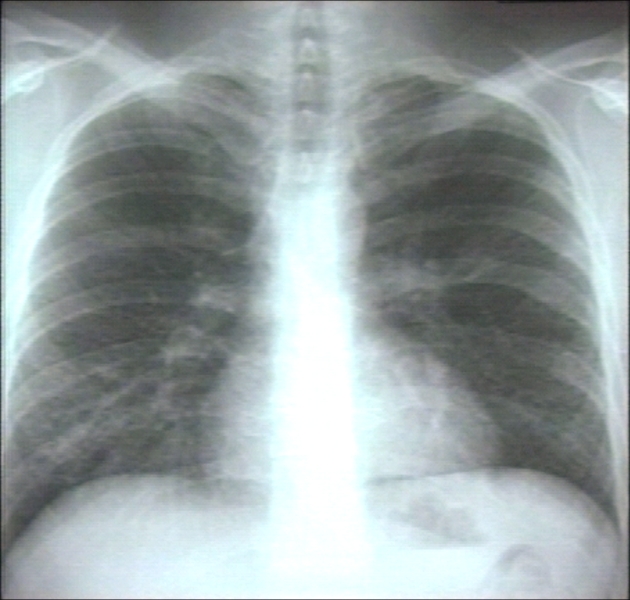

RADIOLOGY: LUNG: SARCOIDOSIS; SUBTLE INCREASE IN DENSITY IN RIGHT PARATRACHEAL AREA,HONEYCombed (PLAIN FILM)